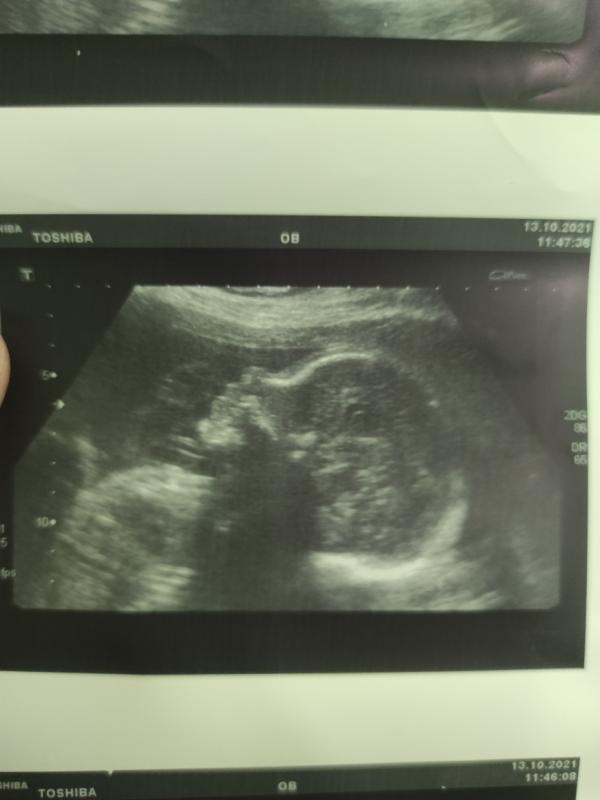

Были на узи у Огай. Все хорошо. 24,5 недель, 788 грамм мой симпатюля!😍 Растем💪 кровотоки в норме! Огай сказала, хорошо, что шейку зашили, она у меня уменьшилась до 30 мм.